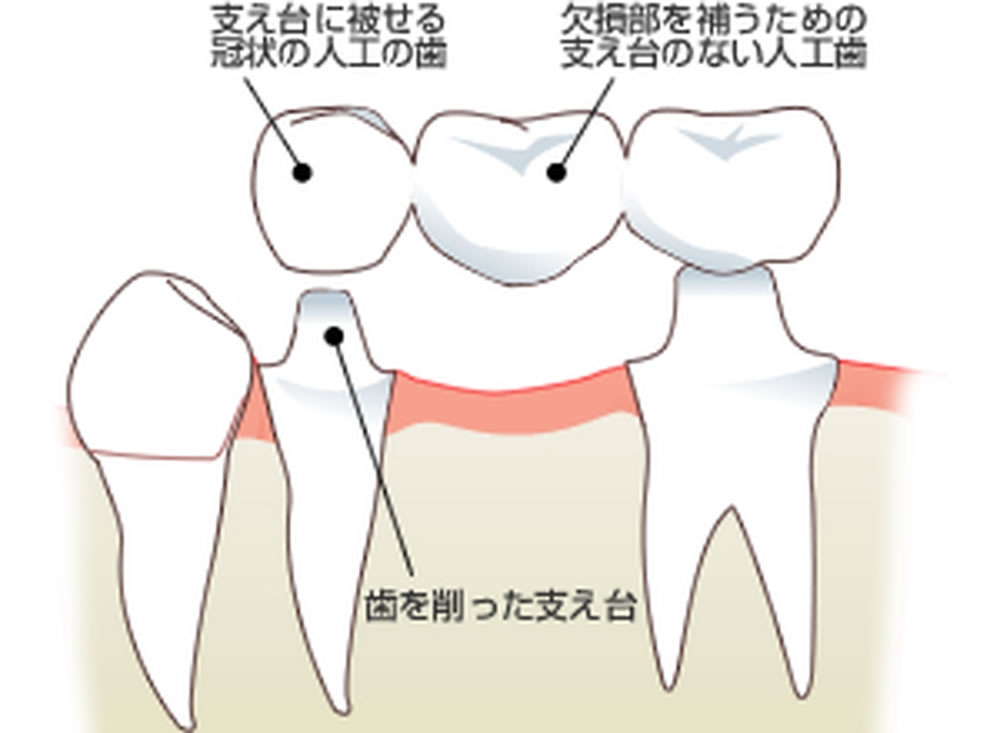

歯の抜け落ちた部分を治す方法は【入れ歯】【ブリッジ】【インプラント】の3つの方法があります。患者様は、なるべく長持ちする方法で治療したいとの事でインプラントをご希望されました。

上記の問題点に加え、骨を作る量が多いので治療期間も非常に長くなることを患者様へお伝えしました。相談の結果、インプラントができないわけではありませんでしたが、数多くの困難な点、術後の不安定性などを総合的に考慮し、ブリッジで咬み合わせを回復することになりました。

ブリッジ治療の実施

ブリッジは通常、欠損した歯の両隣の歯を削り連結させる方法です。

ブリッジは通常、欠損した歯の両隣の歯を削り連結させる方法です。

しかし、今回の患者さまの場合

- ない歯の左隣り(正面から3番目の糸切り歯)は無傷の歯で削るリスクが大きい点。

- 歯周病治療により前歯2本の被せ物と歯肉とのラインに不調和ができている点。

- 前歯2本は被せ物をやり替えたいとの希望があった点。

上記の3点から、前歯2本+欠損した歯の3本分のブリッジで奥に伸ばす設計(延長ブリッジ)としました。もちろんこれにも欠点がないわけではないので、十分に説明し理解をいただいた上で治療を開始しました。